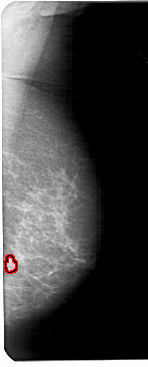

A_1600_1.RIGHT_MLO

RIGHT_MLO LINES 5491 PIXELS_PER_LINE 2206 BITS_PER_PIXEL 12 RESOLUTION 43.5 OVERLAY

FILE: A_1600_1.RIGHT_MLO.OVERLAY

TOTAL_ABNORMALITIES 1

ABNORMALITY 1

LESION_TYPE MASS SHAPE FOCAL_ASYMMETRIC_DENSITY MARGINS ILL_DEFINED

ASSESSMENT 4

SUBTLETY 1

PATHOLOGY BENIGN

TOTAL_OUTLINES 1

BOUNDARY